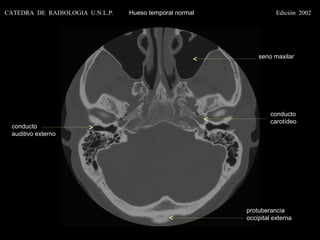

seno maxilar

conducto

carotídeo

auditivo externo

protuberancia

occipital externa